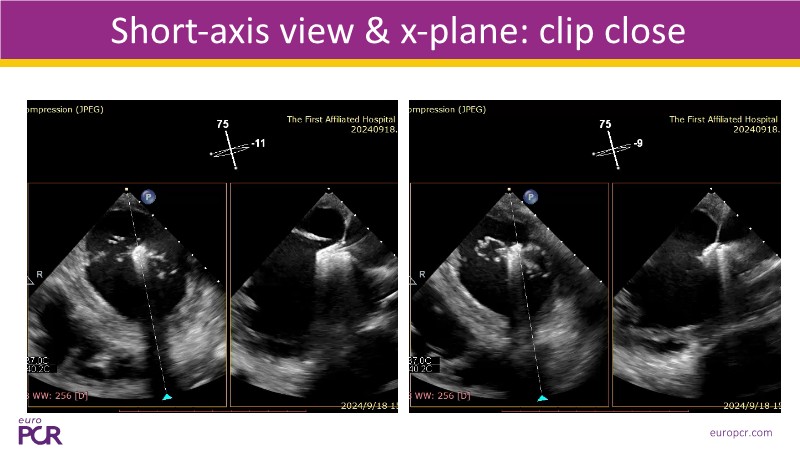

- To discover tips and techniques for mitral TEER in patients with challenging anatomy and difficult imaging